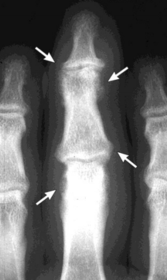

| What disease is this? What do the arrows indicate? | Gout Arrows = 'punched out' erosions |

| What disease is this? What indicates this? | Tophaceous gout. Soft tissue swelling surrounding the index finger PIPJ, with associated erosion and bone resorption |

| What disease is this? | Tophaceous gout. |